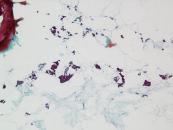

第38回日本臨床細胞学会九州連合会学会(熊本)スライドカンファレンス症例2

種別:呼吸器

出題:白澤 晃樹 鹿児島市立病院病理診断科・病理診断技術科

| 年齢 | 60代 | 性別 | 男性 |

| 採取部位 | 左肺腫瘍 | 採取方法 | 腫瘍部穿刺(呼吸器外科切除検体から採取) |

現病歴:検診時の胸部異常陰影で当院呼吸器内科を紹介受診。

胸部造影CTで左肺下葉に最大径22 mmの腫瘤影。

腫瘍マーカー:CEA : 6.1、SCC : 0.80、NSE : 13.3。

| 正解 | 2.粘液腺腺腫 |

▼選択肢及び投票結果

| 1.過誤腫 | 3件 | (2.9%) | |

| 2.粘液腺腺腫 | 20件 | (19.2%) | |

| 3.粘表皮癌(低異型度) | 63件 | (60.6%) | |

| 4.腺扁平上皮癌 | 0件 | (0.0%) | |

| 5.浸潤性粘液腺癌 | 18件 | (17.3%) | |

| 投票総数 | 104件 | (100%) |